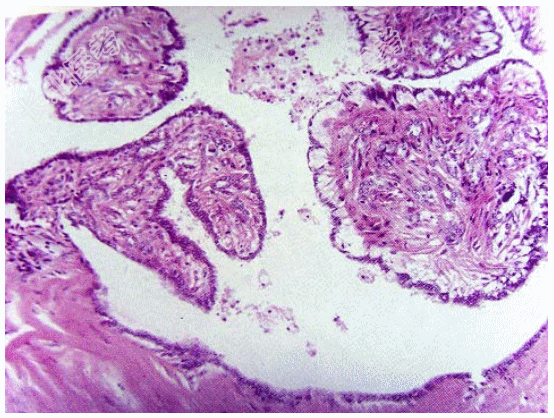

- [材料题] 女性,35岁,左侧乳头血性溢液半月余,乳头附近扪及柔软、樱桃大小包块,尚可活动。超声显示肿块界限清楚,低回声结节。手术切除,显微镜下管腔内见树枝状结构,乳头和导管共存(如图)。临床诊断为导管内乳头状瘤。

- 简答题1、该疾病大体检查表现为?

- 简答题2、该疾病组织学表现表现为?